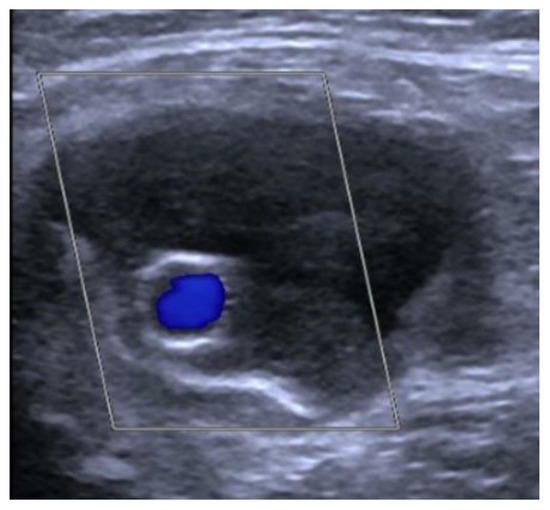

The completion arteriogram showed the resolution of the occlusion with the direct and increased distal flow without any complications (Figure 4a–d). Successful haemostasis with FemoSeal (Terumo Europe) was obtained. The stent graft has adapted perfectly to the morphology of the lesions to be treated. The popliteal artery was reperfused to the third proximal through the collateral vessel; the vessel did not show significant atheromatous plaques. After treatment, the patient underwent therapy with clopidogrel (75 mg) + ASA (100 mg) for 2 months; next with only ASA (100 mg). Color Doppler Ultrasound after 1-3-6-9-12 months from the procedure showed patent self-expanding stent graft inside the excluded PA (Figure 5).

Figure 5. Color Doppler Ultrasound: patent stent graft inside the excluded distal anastomotic PA.